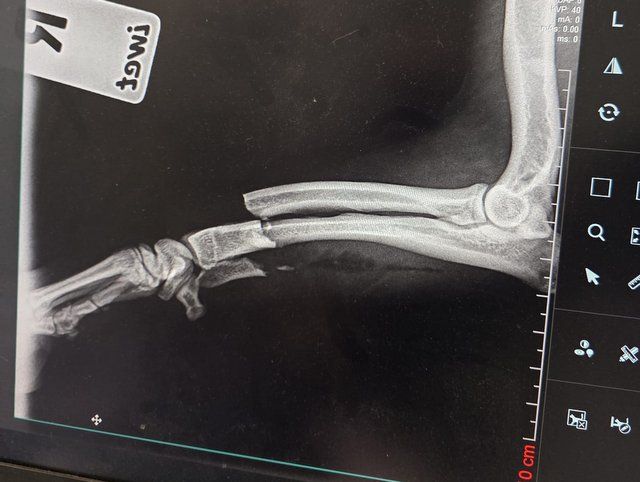

Röntgenbilder zeigten das Ausmaß der Zerstörung des Unterkiefers und den Bruch eines Beines.

Dazu kommt, fast als Nebenbefund, der Beinbruch.

Sein Beinbruch ist ein offener Unterarmbruch von Elle und Speiche, der noch nach Erstversorgung operiert werden muss.